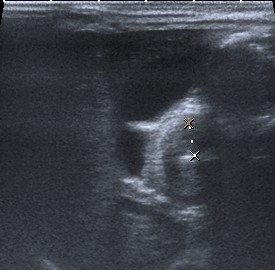

Las sondas que se deben utilizar son las lineales de entre 7-15 MHz (sondas de alta frecuencia). Estas sondas permiten identificar todas las capas de las pared del píloro. A la hora de realizar la prueba es mejor que el estómago se encuentre con poco contenido gástrico. Si el estómago esta lleno de gas se debe poner al paciente en posición oblicua anterior derecha, permitiendo que el líquido gástrico se deposite en el antro por efecto de la gravedad. Un truco es tratar de identificar en primer lugar la vesícula biliar, el píloro suele encontrarse adyacente a la misma.

Visión longitudinal del píloro hipertrofiado. Se encuentra adyacente a la vesícula biliar.

Se consideran diagnósticas un grosor de la capa muscular de 3 mm y una longitud del canal pilórico elongado de 14 mm. En general, ninguna de las medidas es tan importante, porque si el músculo está patológicamente engrosado, el canal estará elongado y fijo por el espasmo sin que se produzca una relajación del píloro para el paso de contenido desde el estómago al duodeno.

Visión axial del píloro hipertrofiado. Mide 6 mm aprox.